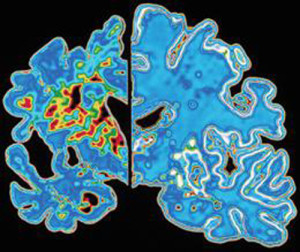

Alzheimer: l’esercizio fisico da solo riesce a dimezzare rischio di demenza

Si tratta del primo studio che ha quantificato l’impatto combinato dei fattori di rischio dello stile di vita sul rischio demenza. Dai risultati e’ emerso che l’esercizio fisico e’ la piu’ grande protezione che abbiamo contro la malattia. Chi fa meno di un’ora di esercizio fisico a settimana, secondo quanto rilevato dai ricercatori, ha l’82 per cento di probabilita’ in piu’ di sviluppare la demenza.

Essere obesi nella mezza eta’, invece, aumenterebbe il rischio di sviluppare l’Alzheimer del 60 per cento, mentre la pressione sanguigna alta aumenterebbe il rischio del 61 per cento. Il fumo, invece, aumenterebbe il rischio demenza del 59 per cento, mentre il diabete del 49 per cento. In pratica, le conclusioni dello studio dimostrerebbero che stili di vita sani che aiutano a mantenere una buona salute cardiaca proteggono anche il cervello. “Anche se non esiste un unico modo per prevenire la demenza, potremmo essere in grado di adottare misure per ridurre il nostro rischio di sviluppare demenza in eta’ piu’ avanzata”, hanno concluso i ricercatori.